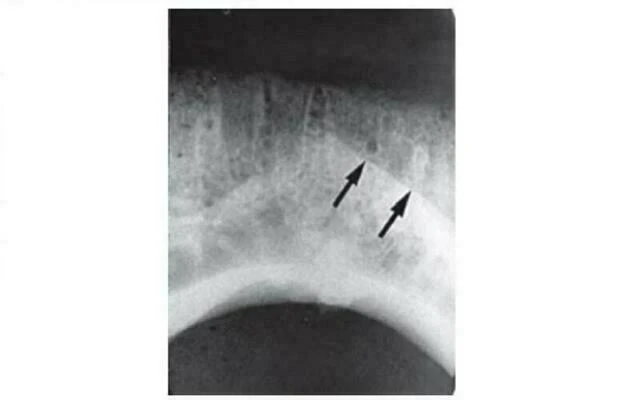

Hình ảnh X quang vùng khớp nối giữa hai bên xương hàm dưới ở trẻ sơ sinh là một đường thấu quang đi qua đường giữa, hai bên là hình ảnh răng cửa giữa đang được hình thành. Đường khớp này thường được cốt hóa vào cuối năm đầu tiên của đời sống, sau đó hình ảnh trên X quang không còn rõ ràng nữa. Thường không thấy hình ảnh này trên X quang răng vì rất ít bệnh nhân nhỏ tuổi cần phải kiểm tra bằng X quang. Nếu hình ảnh thấu quang này thấy được ở những người lớn tuổi hơn thì có thể là một hình ảnh bất thường của gãy xương hoặc khe hở.